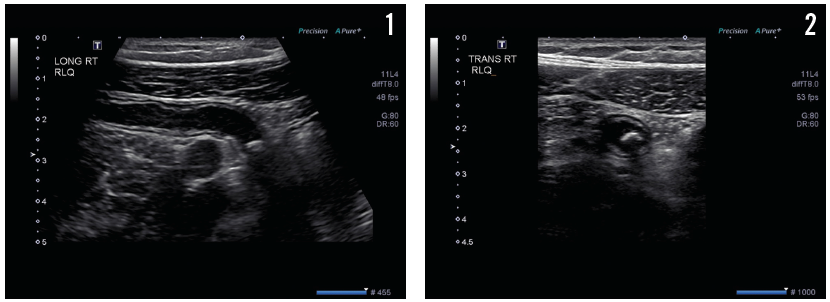

On day 5 of hospitalization, the patient still complained of lower abdominal pain despite opioid analgesics, prompting further ultrasonography scans, the results of which are shown in Figures 1 and 2.

The results of pelvic ultrasonography (Figure 1) showed an elongate, tubular, noncompressible bowel loop in the right lower quadrant, measuring 8 mm, likely representing the appendix with a blind end, and suggesting acute appendicitis with appendicolith but without evidence of perforation. A cross-sectional scan (Figure 2) showed no free fluid or periappendicular fluid collection that would suggest perforation; it also demonstrated the “ring of fire” due to the high vascularity of the inflamed appendix (Figure 3).

Figure 1. Ultrasonography revealed a tubular, elongated, noncompressible bowel loop in the right lower quadrant, measuring 8 mm, likely the appendix with blind end.